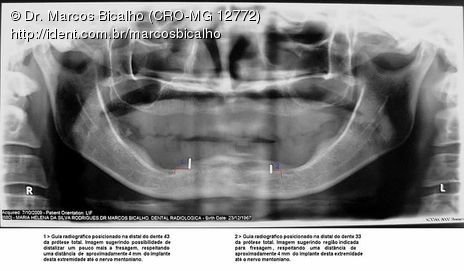

Apesar da boa adaptação e estética satisfatória, a principal queixa da paciente era a instabilidade da prótese inferior, como sempre ocorre nestes casos...atrofia do rebordo alveolar e perda da função mastigatória.